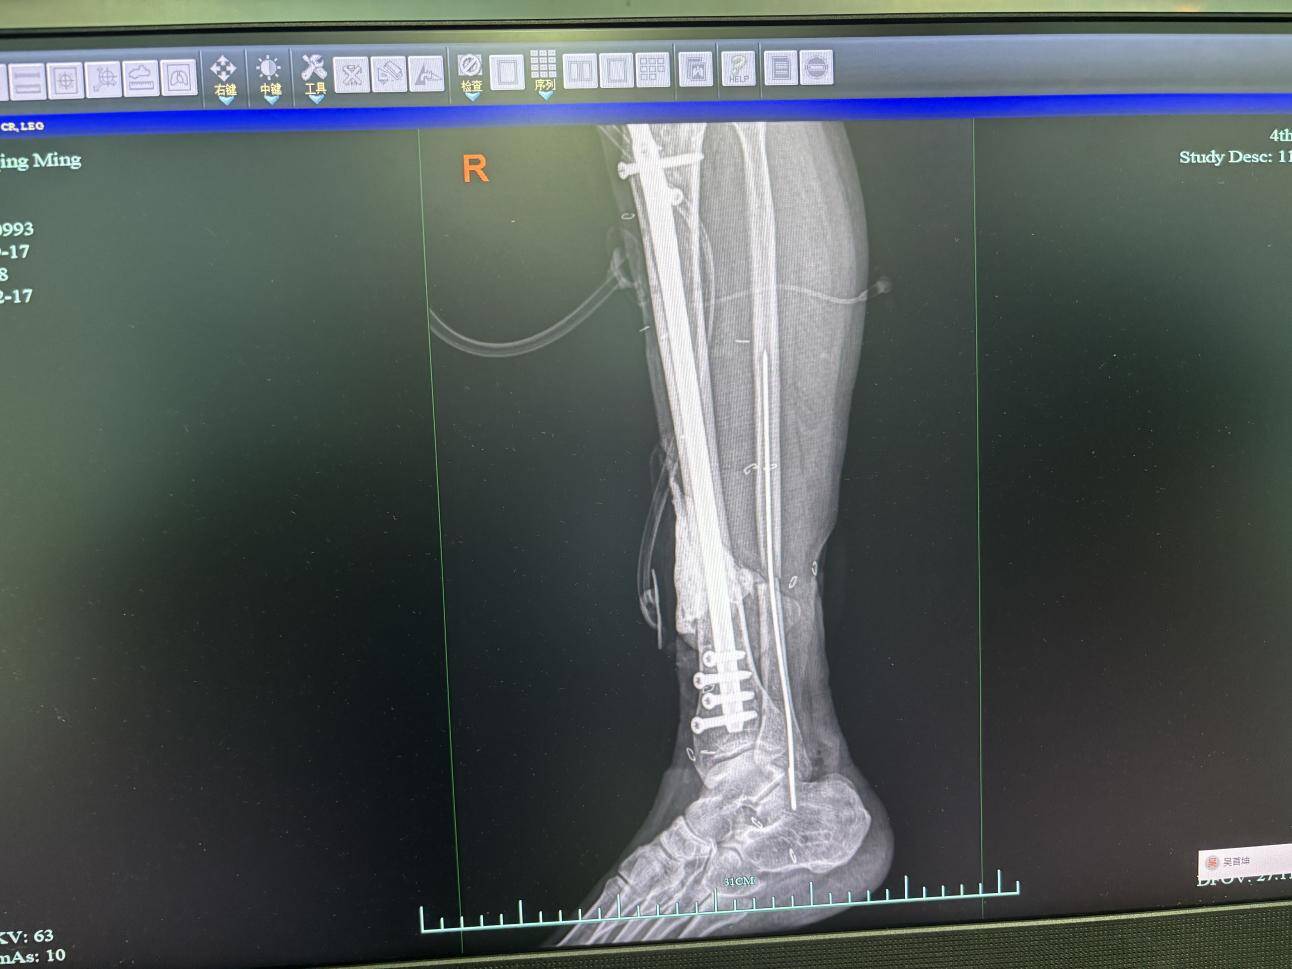

●骨折固定升级:做胫骨骨折闭合复位髓内针固定术。比起之前的外固定,这种方式更符合骨骼的生物力学特点,能让患者更早开始功能锻炼,避免肌肉萎缩。

10月2日复查情况

如今再看老张的腿,创面恢复得很不错,足部恢复了往日红润的样子,足趾也恢复了活性,终于不用再担心截肢的问题。

“下一步,我们将通过手术把缺损的骨折断端补齐,进行植骨填充,这样就能把患者小腿的骨骼结构和运动功能重建好,恢复正常的生活。”李钧说。